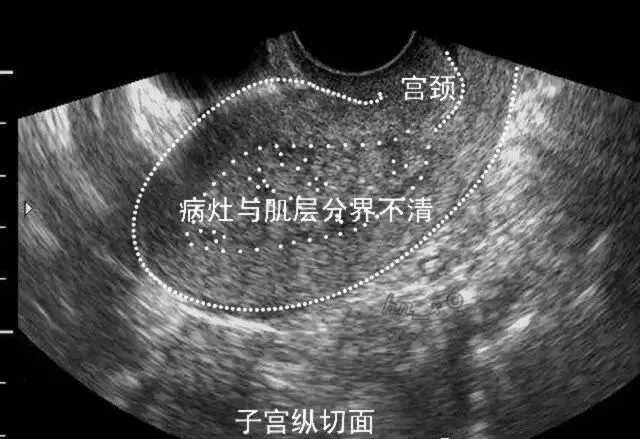

●二维超声表现:子宫内膜增厚、当病变累及肌层时局部内膜与肌层界限不清、早期子宫外形轮廓多无明显改变。

子宫内膜癌侵犯浅肌层声像